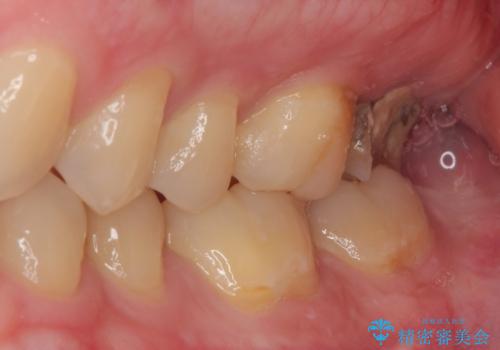

- 他院で虫歯治療の途中の歯を治療したいとのことで来院された患者様です。来院時特に症状もなく、根管治療途中の状態でした。レントゲン上でも大きい病変を認めました。治療方針として再度根管治療を行うか、抜歯をしてインプラントにする二つの方法をご提案しました。

咬み合わせが強く根管治療後の歯の破折のリスクや治療期間の観点からインプラント治療を行っていくこととなりました。

根尖病巣も大きかったため先に抜歯を行い、1ヶ月後にインプラントを埋入しました。